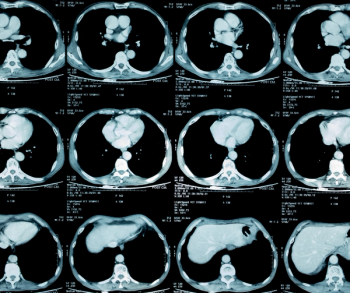

In the newly released Lung-RADS 2022 classification system for computed tomography (CT) lung cancer screening, the American College of Radiology (ACR) has noted a variety of updates including new classification criteria for atypical pulmonary cysts and airway nodules, time intervals for nodule growth and a new stepped management approach for Lung-RADS categories 3 and 4A.